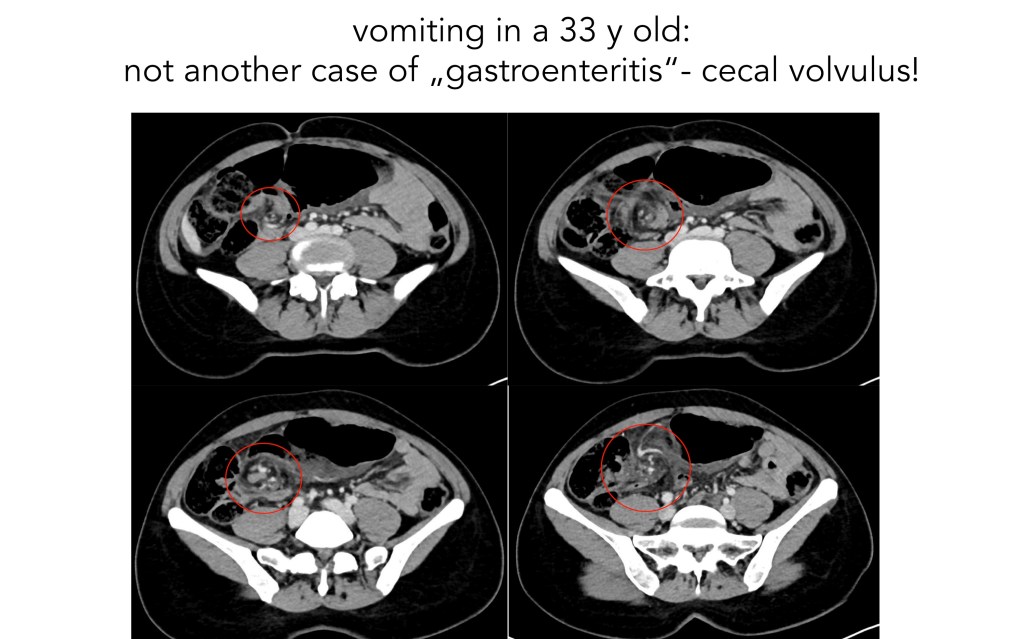

NO gastroenteritis